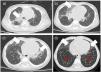

The six cases of NEHI presented here demonstrates that this is one of the children interstitial lung diseases with the most favorable prognosis. The delay in diagnosis may be related to the nonspecificity of the initial respiratory symptoms and the low level of suspicion resulting from the low frequency of the disease,3 and diagnosis is based on the respiratory symptoms assessed by the NEHI clinical score, which manifest between age 1 and 12 months (usually by age 6 months) and the typical chest CT scan features (ground glass opacities predominantly in lingula and/or air trapping with inversion of the normal ventilatory ratio5 (Fig. 1). Although a possible genetic etiology has been hypothesized, a causative gene has yet to be clearly identified, and none of our patients underwent genetic testing. The lung biopsy is reserved for cases with uncharacteristic features.6